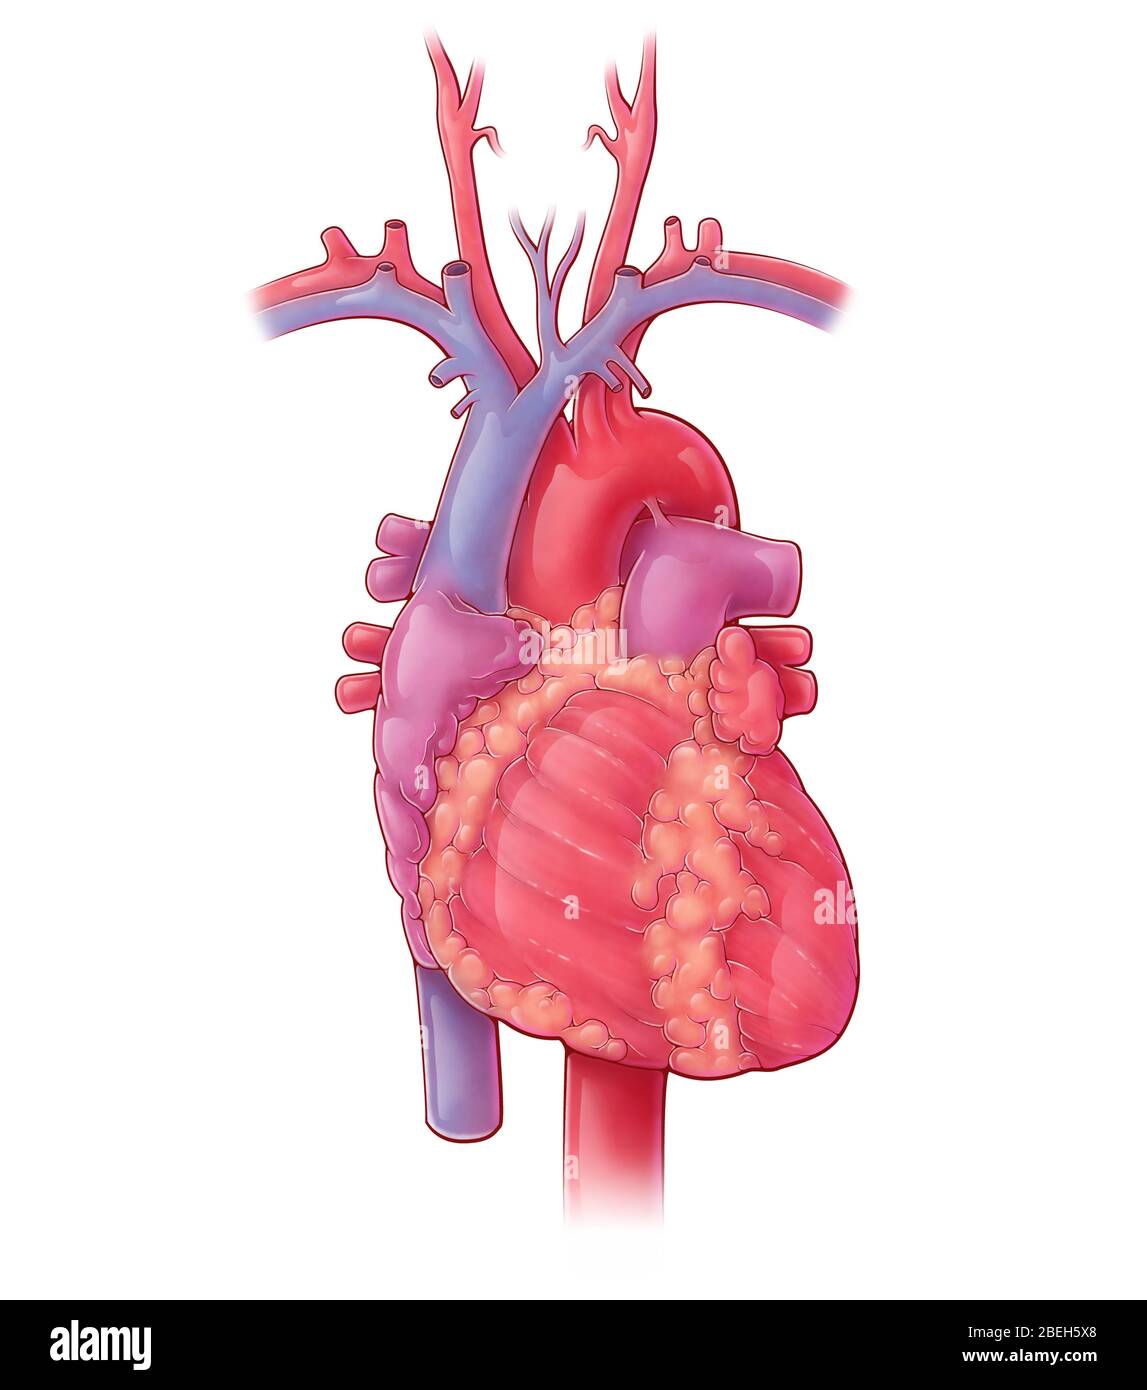

Heart, Illustration Stock Photohttps://www.alamy.com/image-license-details/?v=1https://www.alamy.com/heart-illustration-image353190384.html

Heart, Illustration Stock Photohttps://www.alamy.com/image-license-details/?v=1https://www.alamy.com/heart-illustration-image353190384.htmlRM2BEH5X8–Heart, Illustration